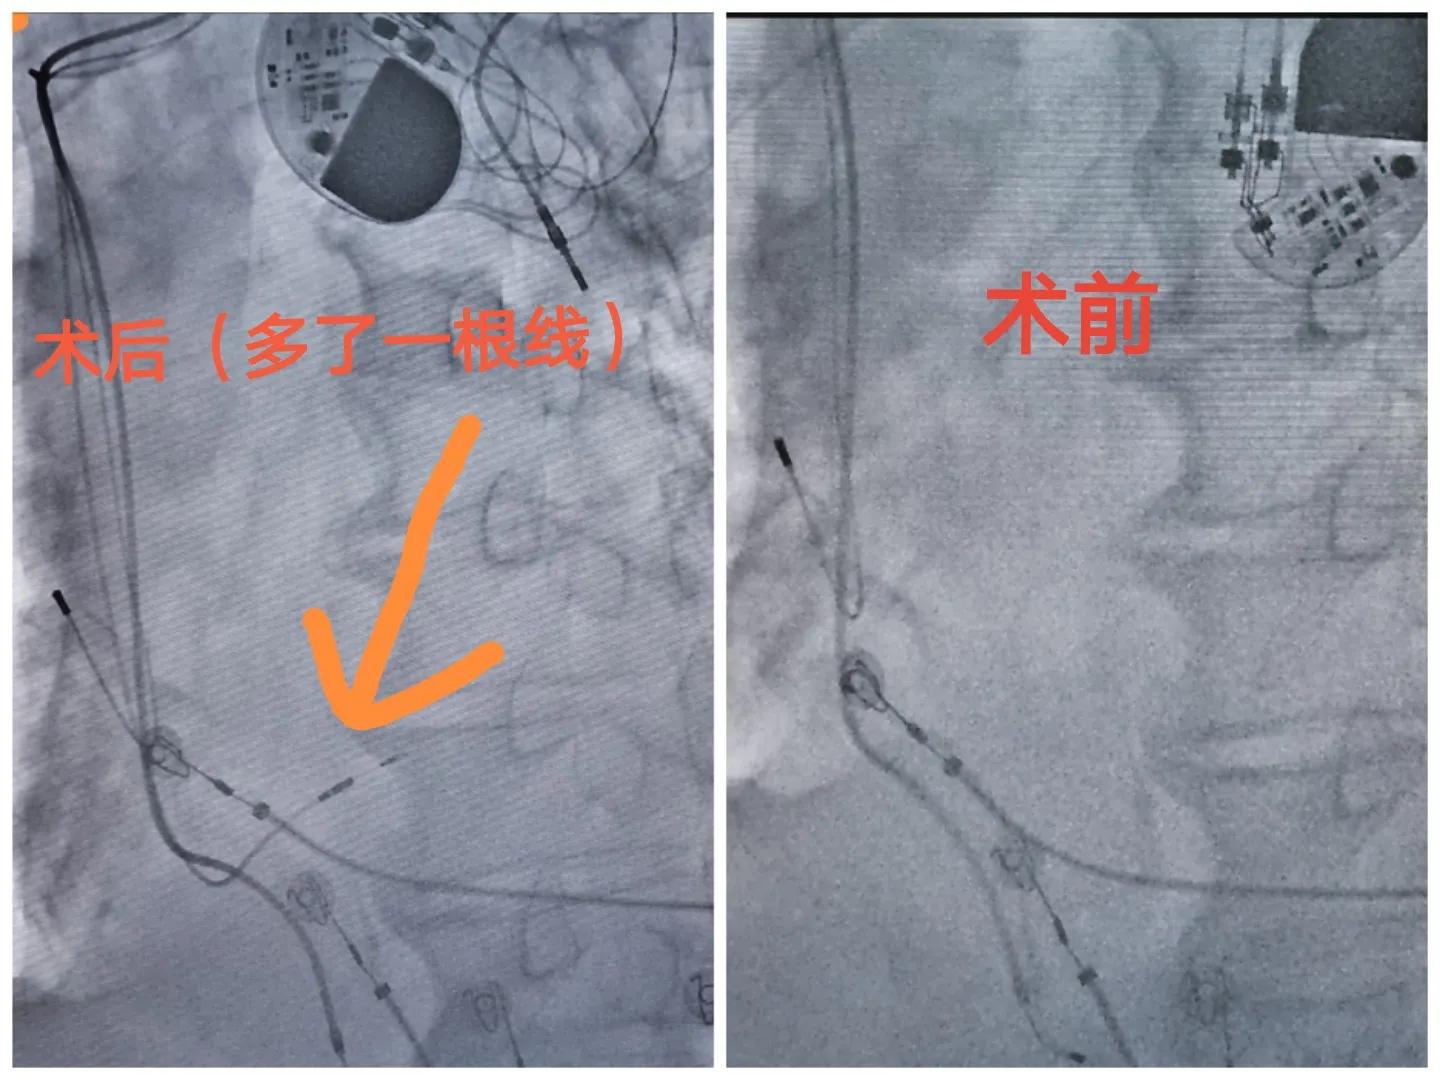

再放一张胸片,双腔起搏器,单极导线,右心耳-右室心尖部起搏导线,左心明显扩大,肺充血改变,同时发现起搏器囊带下移。

看到这里,有一些朋友应该有答案了,起搏器导致的心衰,高比例的右室心尖部起搏导致的心脏非同步化,术前AS-VP,心尖部起搏的QRS宽度达到了192ms,调整AV至350ms,出现了自身下传的QRS波,AV间期长达300多ms,是一个长的一度房室传导阻滞合并完全性左束支阻滞(QRS176ms)。可以行CRT治疗或升级为左束支起搏。

术前程控提示起搏器完全为VAT模式,起搏器最少可使用2.5年(家属考虑年纪大,要求本次一并把“电池”也换了)。